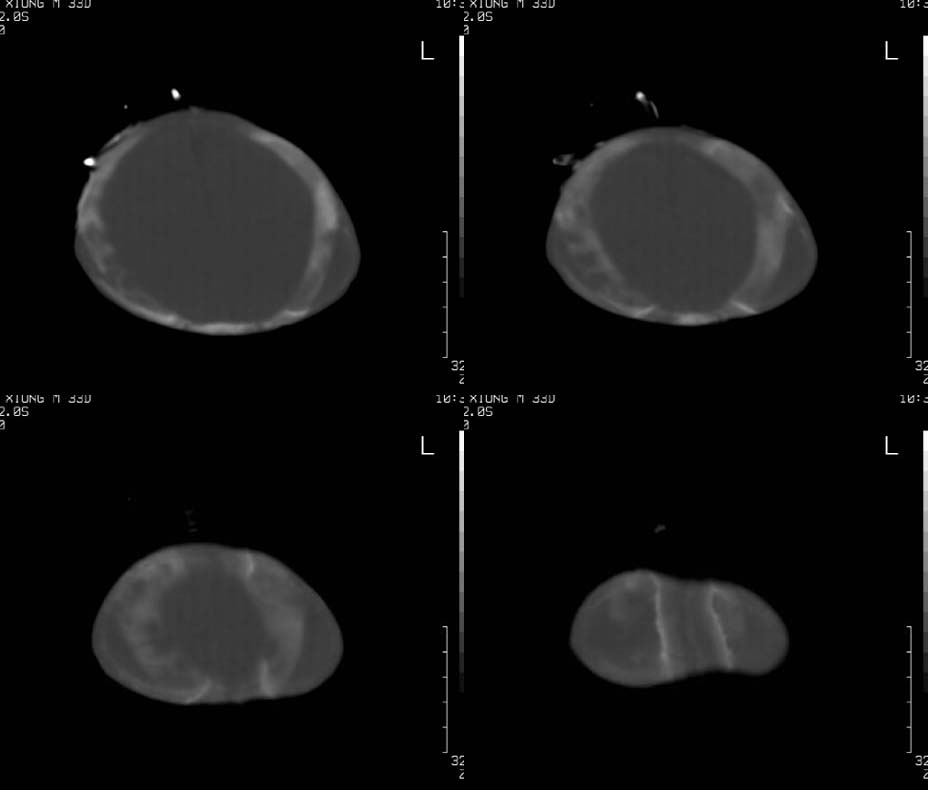

患儿,男,30天。出生时即发现两侧头顶部肿块,触诊似乒乓球样,其余各项检查未见异常。ct扫描:两侧顶骨外侧软组织密度影,ct值约29hu,脑皮质ct值约28.1hu。外缘尚见骨样结构。

双侧顶部头皮血肿(机化、钙化)。

建议结合临床(分娩时是否有胎吸史)